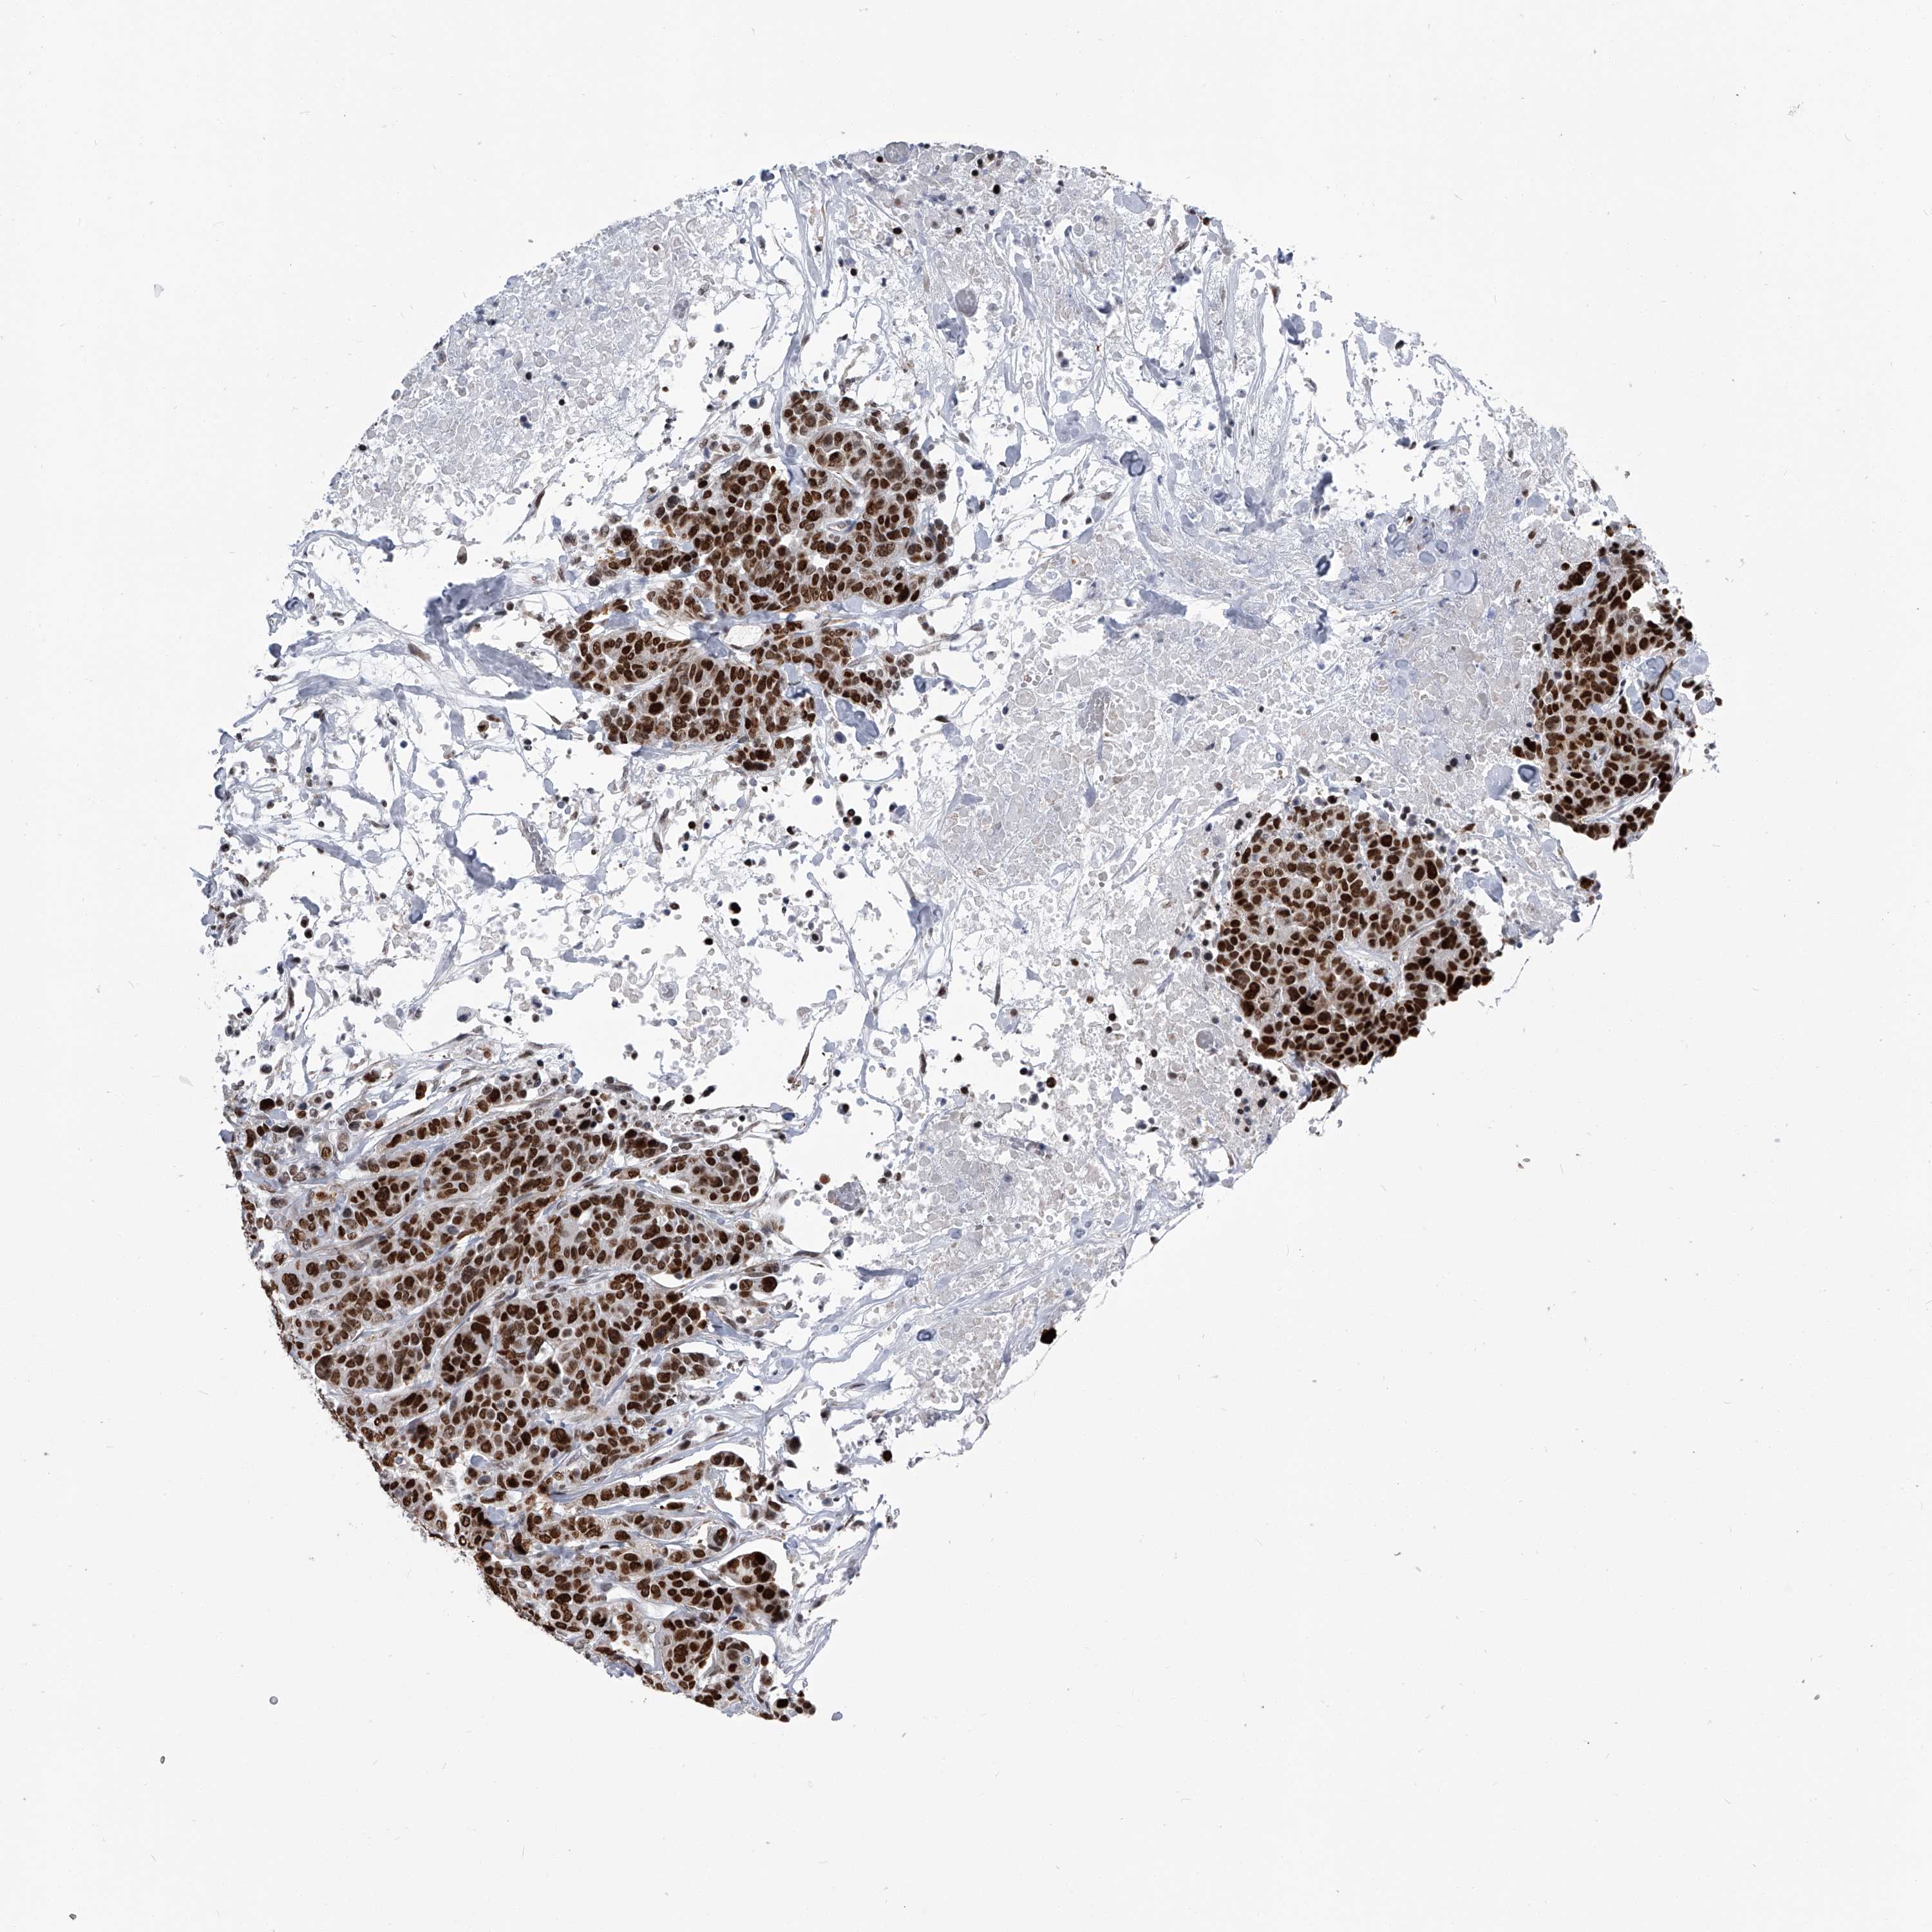

BRCA TCGA BRCA VALIDATION PROTEIN EXPRESSION

ANTIBODIES

AND

VALIDATION